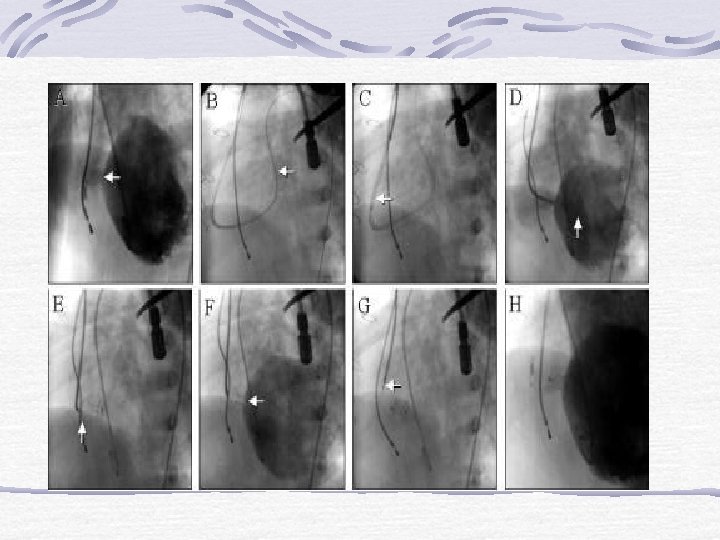

Amplatzer Perimembranöz VSD Cihazı § Aortik disk 0. 5 mm > orta kısım § Sol V alt disk 5. 5 mm > orta kısım § Sağ V disk 2 mm > orta kısım § Sol V diskinde platin bir marker(altta) § Bırakma teli değişik § Femoral venden implant